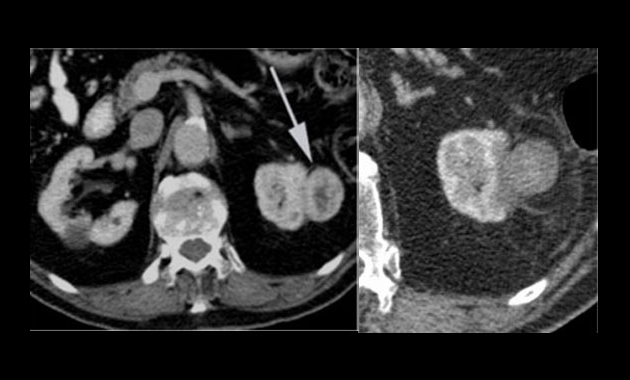

Radiofrequency ablation (RFA) and microwave ablation (MWA) of kidney tumors, or kidney tumor ablation, is an effective alternative to surgical resection for small renal tumors that have not spread beyond the kidney. It is a minimally invasive, nonsurgical procedure with a recovery time of less than 24 hours.

While the patient is under anesthesia or conscious sedation, the interventional radiologist uses computed tomography (CT) to identify the tumor, which has already been identified from prior imaging. Biopsy of the mass, if not already completed, is done at the beginning of the ablation session. Then a thin needle-shaped probe is advanced through the patient’s skin until the tip of the probe is correctly placed inside the tumor. The radiologist then activates the probe—either with an electrical current of radiofrequency or microwave energy or with a cold gas—to create extreme heat or cold around the tip of the probe. The temperature destroys the tumor instantly. The procedure takes two to three hours including preparation time; the actual procedure usually takes an hour or less. The patient will experience some controllable pain for a few hours after the procedure, but the pain typically resolves rapidly with mild medication. The patient is sent home within 24 hours of the procedure and can resume normal activities.